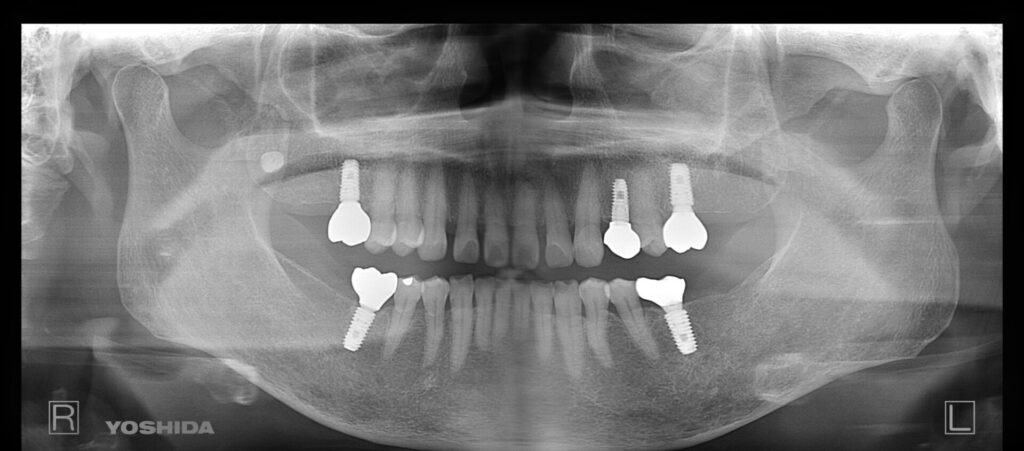

インプラント8年経過

痛みはまぁ大きな問題はなかったのですが、2017年にインプラント治療をして依頼診てなかったので、インプラントがどうなっているかレントゲンを撮ってみました。

上が2017年、下が2025年です。

骨の吸収もなく、見事にそのまま機能しています。

元々骨の条件がよく、プラークコントロールも良かったっていうのはあるのですが、確認できて一安心でした。